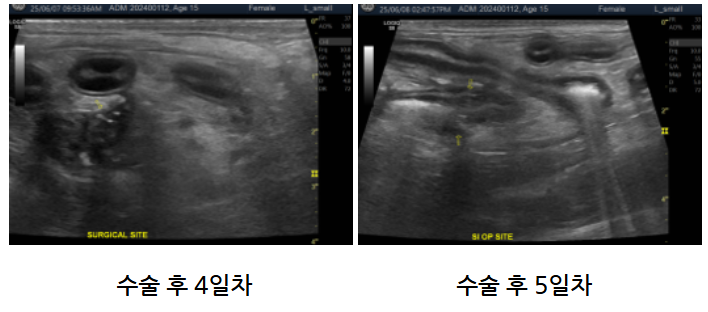

몽이는 수술 후 빈혈 악화 없이 안정적으로 유지되었고, CRP(급성 염증 수치)도 점차 낮아지는 양상을 보여 퇴원했습니다.

귀가 후 연변이 있었으나, 수술 부위를 재확인한 결과 문합 부위에서는 유출이 없었고, 기존에 확인되었던 결장염 소견은 계속 관찰되었습니다.

유산균을 추가로 복용한 이후 변 상태는 개선되었습니다.